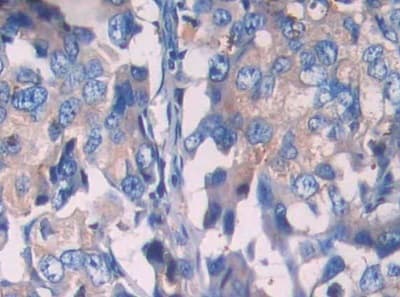

Rabbit Polyclonal SIGIRR antibody. Suitable for WB, IHC-P and reacts with Pig, Human samples. Cited in 1 publication. Immunogen corresponding to Recombinant Fragment Protein within Human SIGIRR aa 1-150.

Applications IHC-P, WB

Species Reactivity Human, Pig